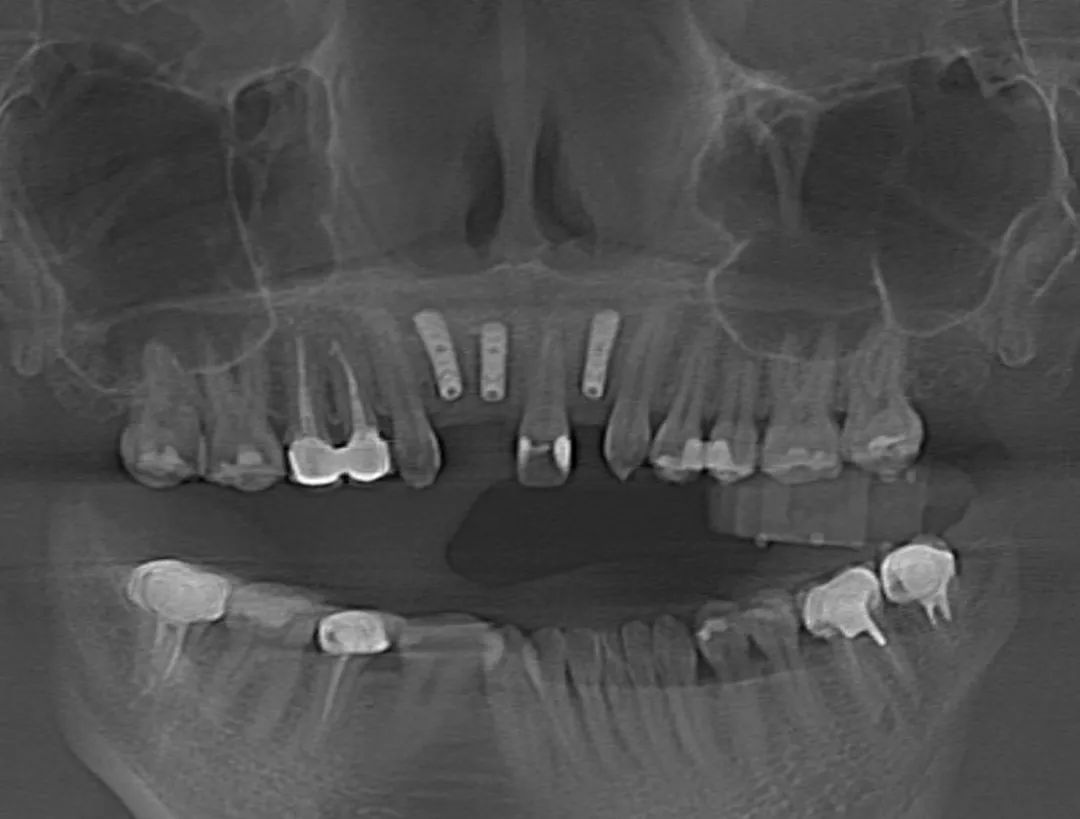

術(shù)前,醫(yī)生將患者的影像學(xué)資料導(dǎo)入機(jī)器人系統(tǒng),進(jìn)行種植體植入全過程的體外可視化模擬,這樣手術(shù)團(tuán)隊(duì)能充分了解患者牙槽骨的骨量及解剖結(jié)構(gòu)走向,更詳盡地制訂手術(shù)方案。術(shù)中,高益鳴主任、李小曼醫(yī)生共同按既定方案,在機(jī)器人全自動模式下,精準(zhǔn)標(biāo)定種植位點(diǎn)并逐級擴(kuò)孔備洞。而且,機(jī)械臂的減速區(qū)設(shè)定,讓機(jī)器人在入口時動作不會過快,“溫柔”且“迅速”地有序按照指令進(jìn)行手術(shù)。手術(shù)過程相比傳統(tǒng)方式來說縮短了近一半。如今,這位女士恢復(fù)良好。

其實(shí),手術(shù)過程中,患者頭部肯定會有輕微移動,而此次使用的“瑞醫(yī)博”口腔手術(shù)機(jī)器人(Remebot Dental Robot)是首款獲國家藥品監(jiān)督管理局(NMPA)認(rèn)證的口腔領(lǐng)域手術(shù)機(jī)器人,它具備的機(jī)器人隨動功能,可以檢測患者位移,保證下鉆過程中軸向準(zhǔn)確性,加上虛擬影像空間和實(shí)際機(jī)器人空間的映射匹配,實(shí)現(xiàn)手術(shù)信息實(shí)時共享,確保預(yù)備窩洞及植入植體精確至毫米級水平,使手術(shù)精度控制在1°和0.5mm以內(nèi)。隨著數(shù)字化口腔的發(fā)展,口腔治療將會迎來更多可能,成為實(shí)現(xiàn)精準(zhǔn)、微創(chuàng)、智能化醫(yī)療的重要組成部分。